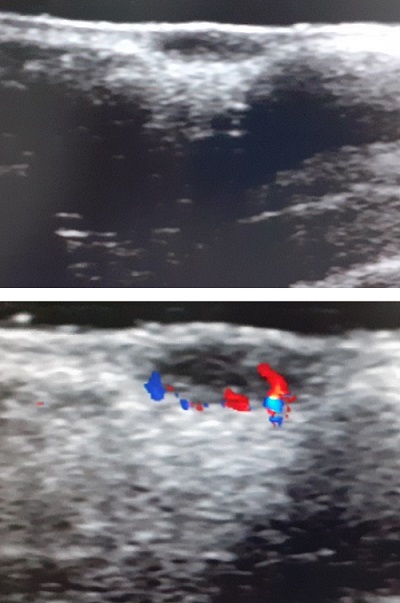

Se solicitó una ecografía de partes blandas, que mostró una lesión nodular circunscrita hipoecogénica de 6,9 x 2,2 mm a nivel dérmico bien delimitada, sin calcificaciones, con algún flujo vascular periférico (Fig. 2).

| Figura 2. Imágenes ecográficas: lesión nodular hipoecogénica, sin calcificaciones y con flujo vascular periférico |

En la ecografía de la lesión se observa una lesión hipoecoica sólida ovalada bien delimitada que afecta a la dermis, con un eje mayor paralelo a la superficie cutánea sin depósitos de calcio en su interior6,9. Rodríguez et al.5 plantea que el GAFI tiene un patrón ecográfico característico según su momento evolutivo. En la fase activa aparece un aumento del flujo sanguíneo peri o intralesional y ecogenicidad aumentada de la hipodermis, mientras que en la fase de involución disminuye el grosor y la vascularización de la lesión.